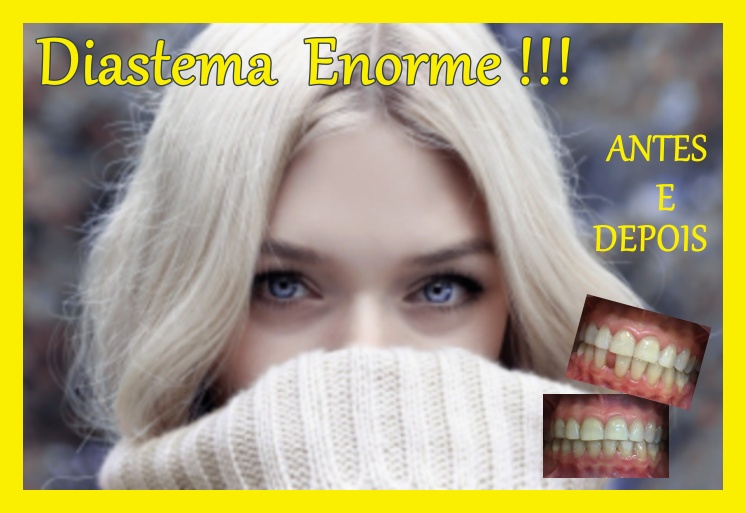

Antes e depois com tratamento ortodôntico

Oferecemos ortodontia para o tratamento,pois o diastema era enorme.

Não ficaria bonito alargar os dentes anteriores.

Então as facetas foram descartadas.

Colocar mais um incisivo também ficaria anti-estético.

A paciente queria um tratamento rápido.

Optou por aparelho ortodôntico autoligado.

O aparelho ortodôntico convencional seria mais demorado,e o invisalign teria uma parcea mais alta.

O tratamento durou 12 meses.

Fizemos ortodontia autoligada fechando todos od diastemas até os dentes caninos.

O dente após o canino, no caso o 1o premolar faremos o fechamento com resina.

Optamos por isso,pois de outra forma seria muito longo o tratamento.

Ao final do tratmento foi feita contenção com barra lingual colada.

Dessa forma ela mantém os dentes em posiçao.

Aqui temos um antes e depois de diastema fechado com restauração de resina